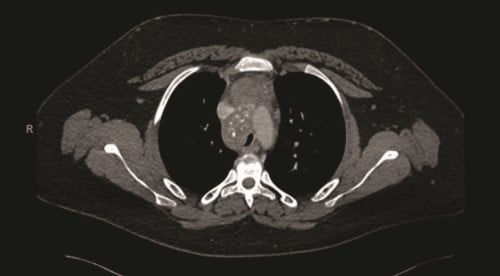

A contrast-enhanced computed tomography (CT) scan of the chest revealed a confluent calcified tissue density mass surrounding the subcarinal, right peritracheal, and anterior mediastinal region, causing significant extrinsic compression of the mid and distal trachea and right main stem bronchus, narrowing of the pulmonary artery, and partial encasement of the azygos vein.

CT of the chest with contrast showed a partially calcified soft tissue mass in the right paratracheal region, extending around the inferior trachea, carina, and proximal mainstem bronchi. The mass measured approximately 8.1 x 6.2 x 7.6 cm.